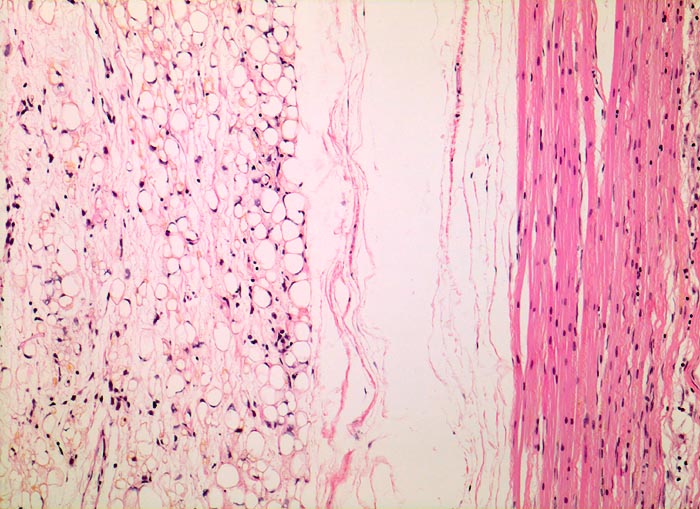

• Am rechten Rand des Präparates komprimierte Skelettmuskulatur.

• Links daran angrenzender scharf begrenzter Tumor mit reichlich myxoidem Stroma.

• Zahlreiche, überwiegend univakuoläre Lipoblasten. Zellkern durch die Lipidvakuole komprimiert und zur Seite verdrängt.

• Zahlreiche krähenfussartig verzweigte Kapillaren.